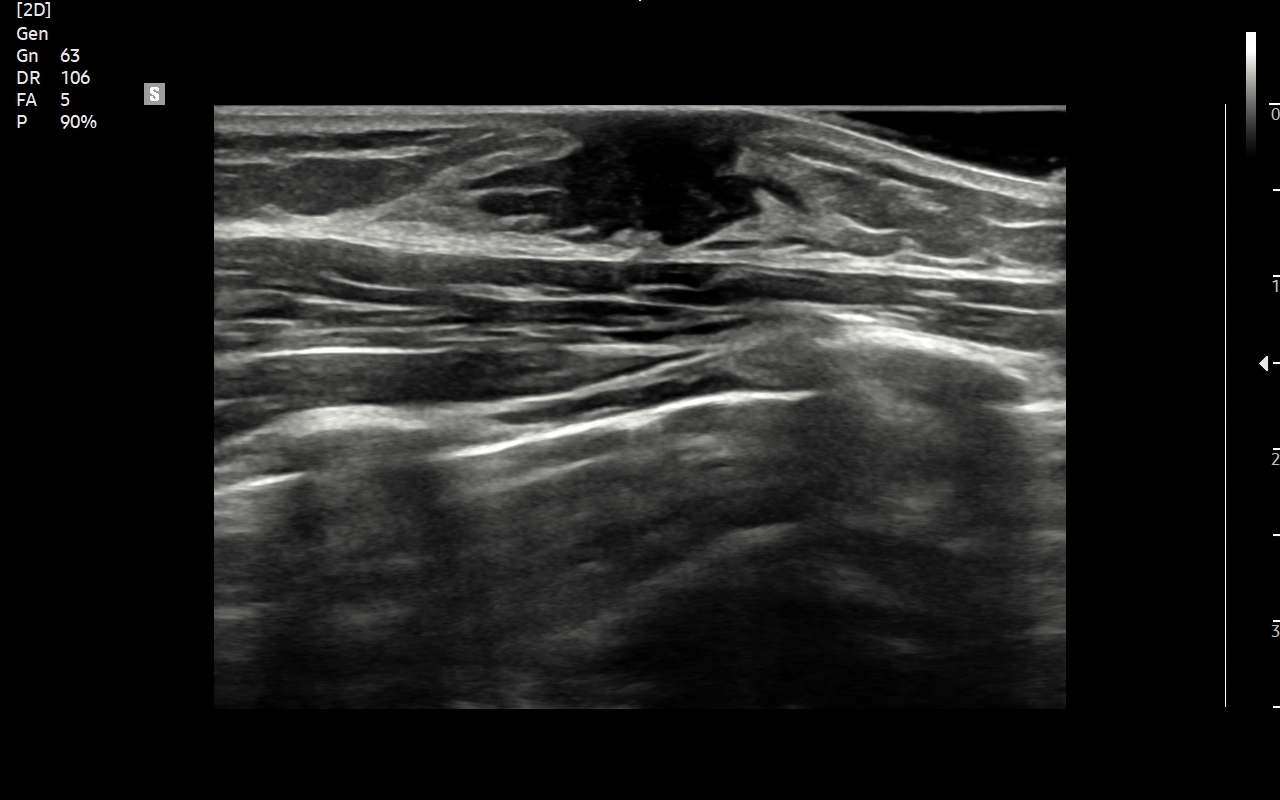

USG piersi z implantami

Badanie USG piersi z implantami jest szczególną procedurą diagnostyczną. Przeprowadza się ze wskazań wcześniej opisanych, jak w przypadku piersi bez implantów, ale także w schorzeniach ściśle związanych z implantem. Przykładami są powikłania chirurgiczne takie jak przemieszczenie się implantu, krwiak, ropne zapalenie tkanek wokół implantu, jego pęknięcie, a także wystąpienie chłoniaka BIA-ALCL (ang. breast implant associated anaplastic large cell lymphoma) jako odległego powikłania wszczepienia implantu piersi.